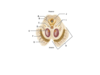

What is A?

Body

What is B?

Genu

What is C?

Rostrum

What is D?

Spleenium

What is E?

Septum pellicidum

What is F?

Fornix

What are the black spaces at each side?

Lateral ventricles